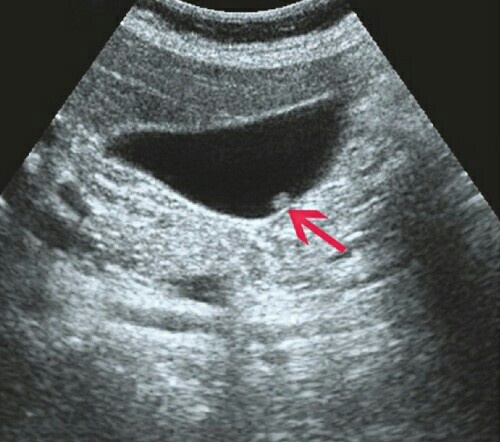

Как то три года назад, ради спортивного интереса сделал УЗИ всех органов в платной клинике, акция была, обошлось всё в 5 тысяч рублей. Всё хорошо, всё нормально, здоров как бык. Но есть нюанс. Обнаружили полипы в желчном пузыре, сразу спросили хочу ли я на операцию, удалить желчный. Я говорю: - а разве можно по другому, операцию нехочу делать! На что и был упор. Сказали ещё не запущенная стадия и нужно проверяться раз в два месяца. Стоимость уже без акций 400 рублей за УЗИ желчного пузыря. Я согласился, придерживаюсь правила что органов лишних нет в организме. В общем делал я каждые два месяца три года УЗИ. И каждый раз ходил и опасался, что вдруг подрастут и резать будут. Ведь выйдешь из строя точно на месяц как не больше, не работы не денег. Там говорили что полипы не растут, что мне везёт и они без изменений. Попал я значит в больницу с желтухой, по выздоровлению делали узи печени, я настоял что бы и желчный проверили, полипы мои. Они говорят что нет никаких полип, и небыло. Вот это

Но есть нюанс. Обнаружили полипы в желчном пузыре, сразу спросили хочу ли я на операцию, удалить желчный.

Там говорили что полипы не растут, что мне везёт и они без изменений.

Попал я значит в больницу с желтухой, по выздоровлению делали узи печени, я настоял что бы и желчный проверили, полипы мои.

Они говорят что нет никаких полип, и небыло.

Полипы нашли! Я достаю снимок с бесплатной больницы, начинаю ругаться, они ничего нехотят слушать, говорят что они в данный момент ошиблись, типо врач молодой неопытный, денеги вернули в этот раз, а так полипы рассосались, я требовал за три года деньги, они не в какую.